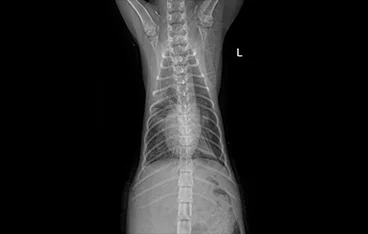

• 횡격막탈장

• 횡격막탈장 수술 전

횡격막탈장 수술 후